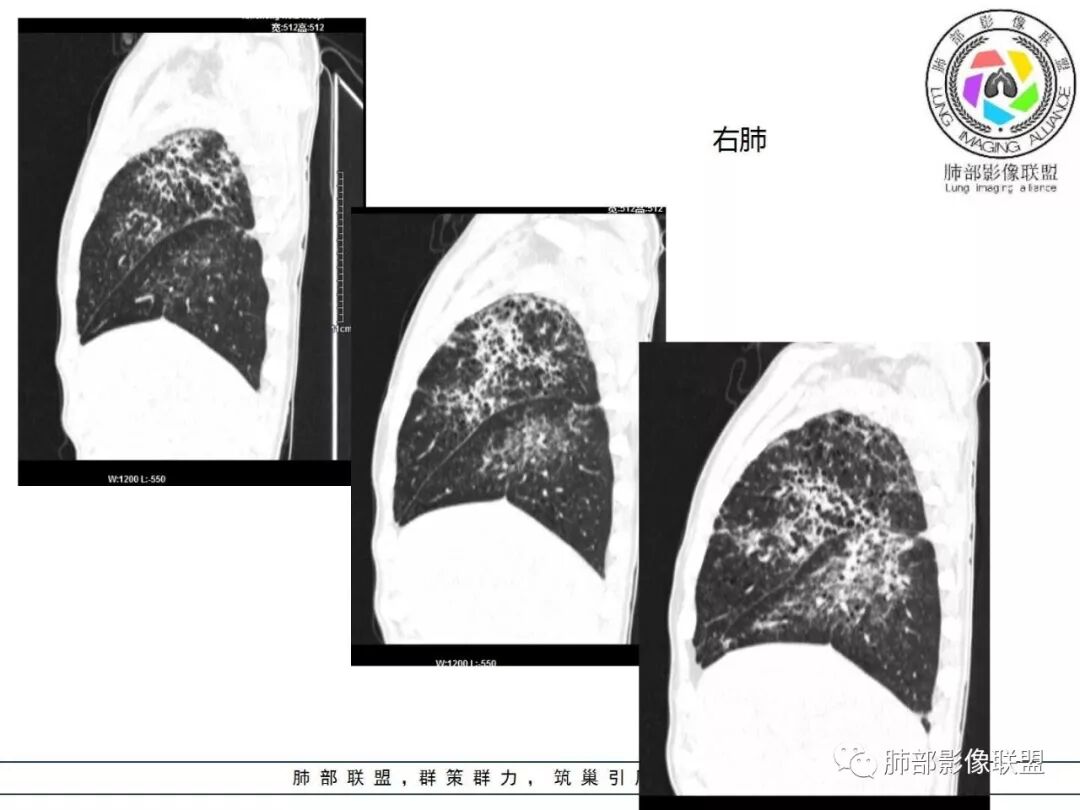

两肺肺气肿,弥漫GGO+实变影,局部伴牵拉性支扩,分布无规律。左侧胸膜明显增厚。双肺门淋巴结钙化。

双肺弥漫性病变,多发磨玻璃密度及小叶间隔增厚,大部分沿支气管血管束分布,伴支气管轻度扩张,以午后及晚上发热为主,考虑感染性病变,间质性结核可能大,另双肺多发肺气囊,LIP待排

中老年男性,双肺弥漫性病变,呈网状、斑片及大片状,实变影及磨玻璃影相间,部分病灶区支气管扩张,并见多发小囊状或蜂窝状透亮影,中央间质增厚,气管前单发小淋巴结。考虑淋巴细胞增生性病变?粘膜相关性淋巴瘤(MALT)或淋巴细胞间质性肺炎(LIP)?鉴别机化性肺炎(OP)及结核(TB)。

两肺弥漫病灶,中央间质分布为主,部分位于胸膜及叶间裂旁,磨玻璃影,斑片影,部分实性结节,肺气囊,支气管血管束增粗,小叶间隔增厚,叶间裂不均匀增厚。考虑:间质性肺病,LIP,鉴别OP

双肺多发斑片,小结节影,支气管血管周围分布为主,部分胸膜下分布,中央间质增厚,部分支气管牵拉扩张。考虑淋巴增殖性病变,lip?结节病?

两肺弥漫性病变,沿支气管血管束分布,部分细支气管轻度扩张,两上中肺为主,部分累及胸膜下,部分磨玻璃影,部分纤维化,肺气肿肺大疱背景,胸膜增厚,少量积液,病程一月余,crp高反复发热,两肺门区增大钙化淋巴结,间质性疾病,考虑淋巴增殖性病变为主,结核可能性大,待鉴别NTM,结节病,LIP,PCP纤维化

病灶呈片状磨玻璃密度影,呈典型的烟花征。磨玻璃影密度偏高,有网结节样改变,与正常肺实质分界清楚,且常见相对高密度的勾画。

烟花征分为3肿类型:晕征、反晕征及均匀分布。

病变一般沿血管支气管束分布或小叶分布,一般上肺多于下肺(这与常见继发性肺结核分布相若)。

2. 肺气肿背景(小叶中心性肺气肿);双肺多发病灶整体沿血管支气管束及胸膜下分布,以上叶及下叶背段分布为主,有实变及GGO,边界清楚,有树芽,小叶间隔及中央间质增厚,叶间裂见到多发结节,部分支气管不规则牵拉扩张,提示病灶纤维化明显,结合临床病史,考虑病灶为间质性感染,肺门及纵隔内有钙化淋巴结,小叶间隔结节,考虑淋巴道增值性疾病可能,综合常规要怀疑间质性肺结核。